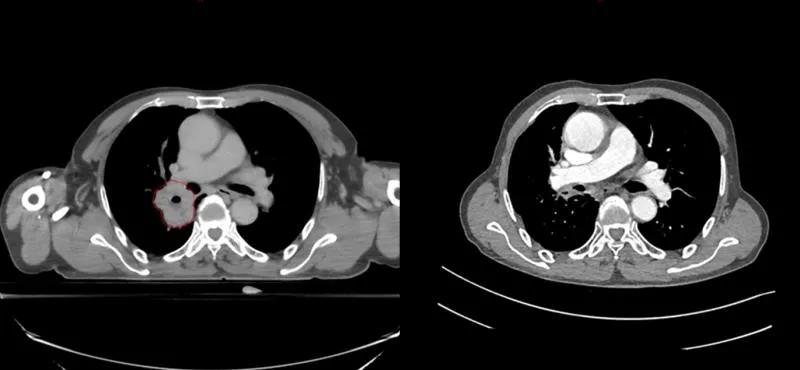

与这些名人患肺癌的同时,笔者治好了至少5位晚期肺癌病人(见下图CT片显示的肿瘤)。笔者病人有咳嗽,咯血,胸痛,胸闷,气急等症状,病人家属知道亲人是晚期肺癌,没有抱多大希望,治疗的目的只是想减轻一些症状,延长生命。经过笔者的精心治疗,2例现已活了5年多,2例已活过3年多,1例已活过2年多。治疗时年龄最大有82岁,最小年龄51岁,他们现在都生活得很好,甚至一个来自江西农村的病人一直在田地里干重体力农活。

治疗前后CT对比,红色为肿瘤(左),治疗后肿瘤消失(右)